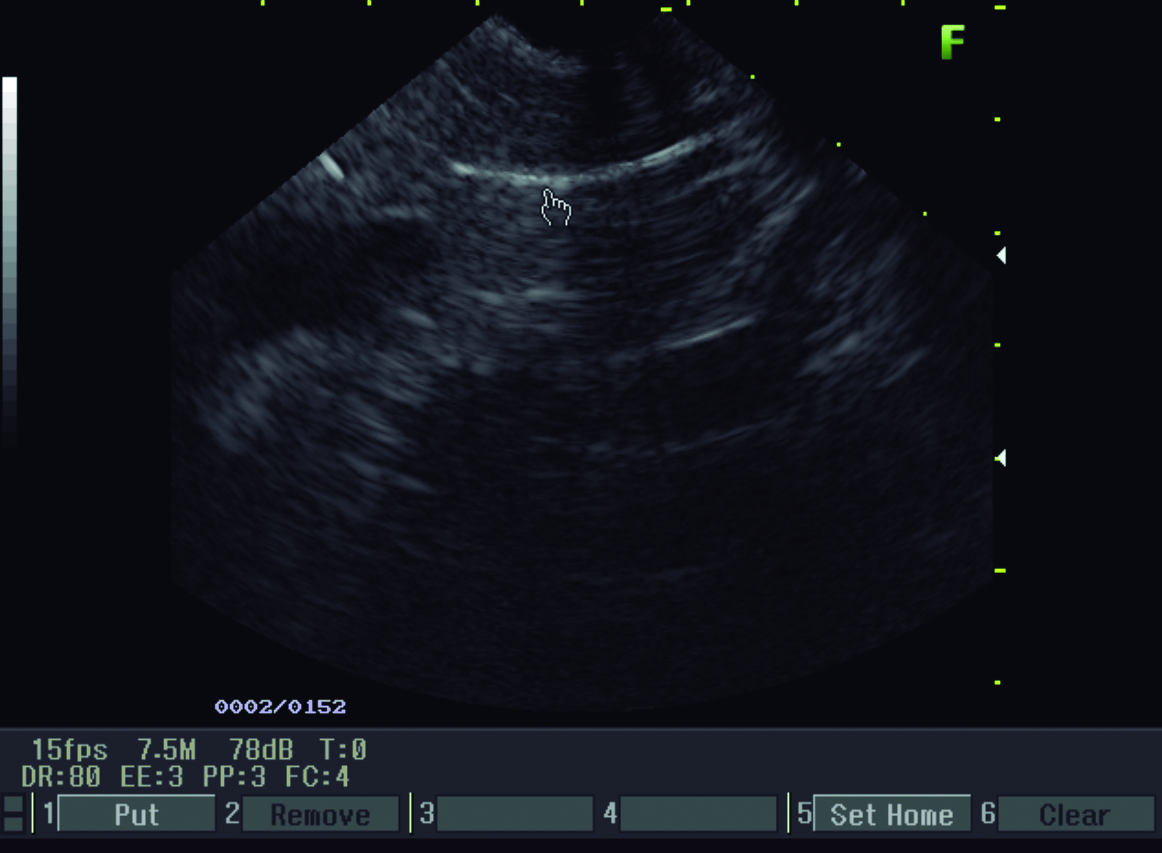

Una semana después se realiza ecoendoscopía digestiva alta, la cual informa colédoco de 9 mm de diámetro, en cuyo interior se observan dos líneas hiperecoicas alargadas, paralelas de unos 3 mm de diámetro total, compatible con Ascaris (Fig. 3).

Figura 3. Ecoendosopía

a y b) Líneas hiperecoicas alargadas, paralelas de 3 mm de diámetro compatible con Ascaris (mano).

En el ultrasonido, la apariencia de los helmintos depende de la sonda empleada. Con transductores convexos de baja frecuencia se visualizan típicamente en un corte longitudinal como una imagen trilaminar y sin sombra acústica, las líneas ecogénicas externas corresponden a las paredes del parásito y la imagen lineal ecogénica en su interior corresponde al tracto digestivo del mismo. Si se visualizan transversalmente en un conducto biliar dilatado, aparecen como una imagen tubular, en diana con bordes ecogénicos y centro anecogénico. Con una sonda lineal de alta frecuencia (mayor a 7.5MHz) los helmintos se observan en corte longitudinal como una imagen de 4 líneas, representando las dos exteriores la interfaz entre el parásito y lo que lo rodea y las dos interiores el intestino de la lombriz. (5, 7, 13) Estas imágenes características fueron las que llevaron al diagnóstico en la paciente que se presenta en este caso. Algunas veces puede observarse la movilidad de los helmintos vivos, pueden estar enrollados y si son múltiples, pueden llenar completamente el conducto biliar y producir el “signo de espagueti”. Si están muy compactados en los conductos biliares, pueden aparecer amorfos y manifestarse como pseudotumores hiperecogénicos. (6) Debe realizarse exploración de la vía biliar principal y accesoria ya que en ocasiones se ubican dentro de la vesícula biliar. También debe valorarse el conducto pancreático para descartar Ascaris en esta localización. El empleo de la sonda lineal en ocasiones es de utilidad para mejorar la resolución espacial y de ese modo caracterizar mejor los parásitos. (1)